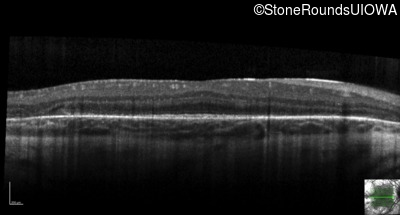

Optical Coherence Tomography - Right - 20/32

Exemplar / OCT Stack

OCT Stack